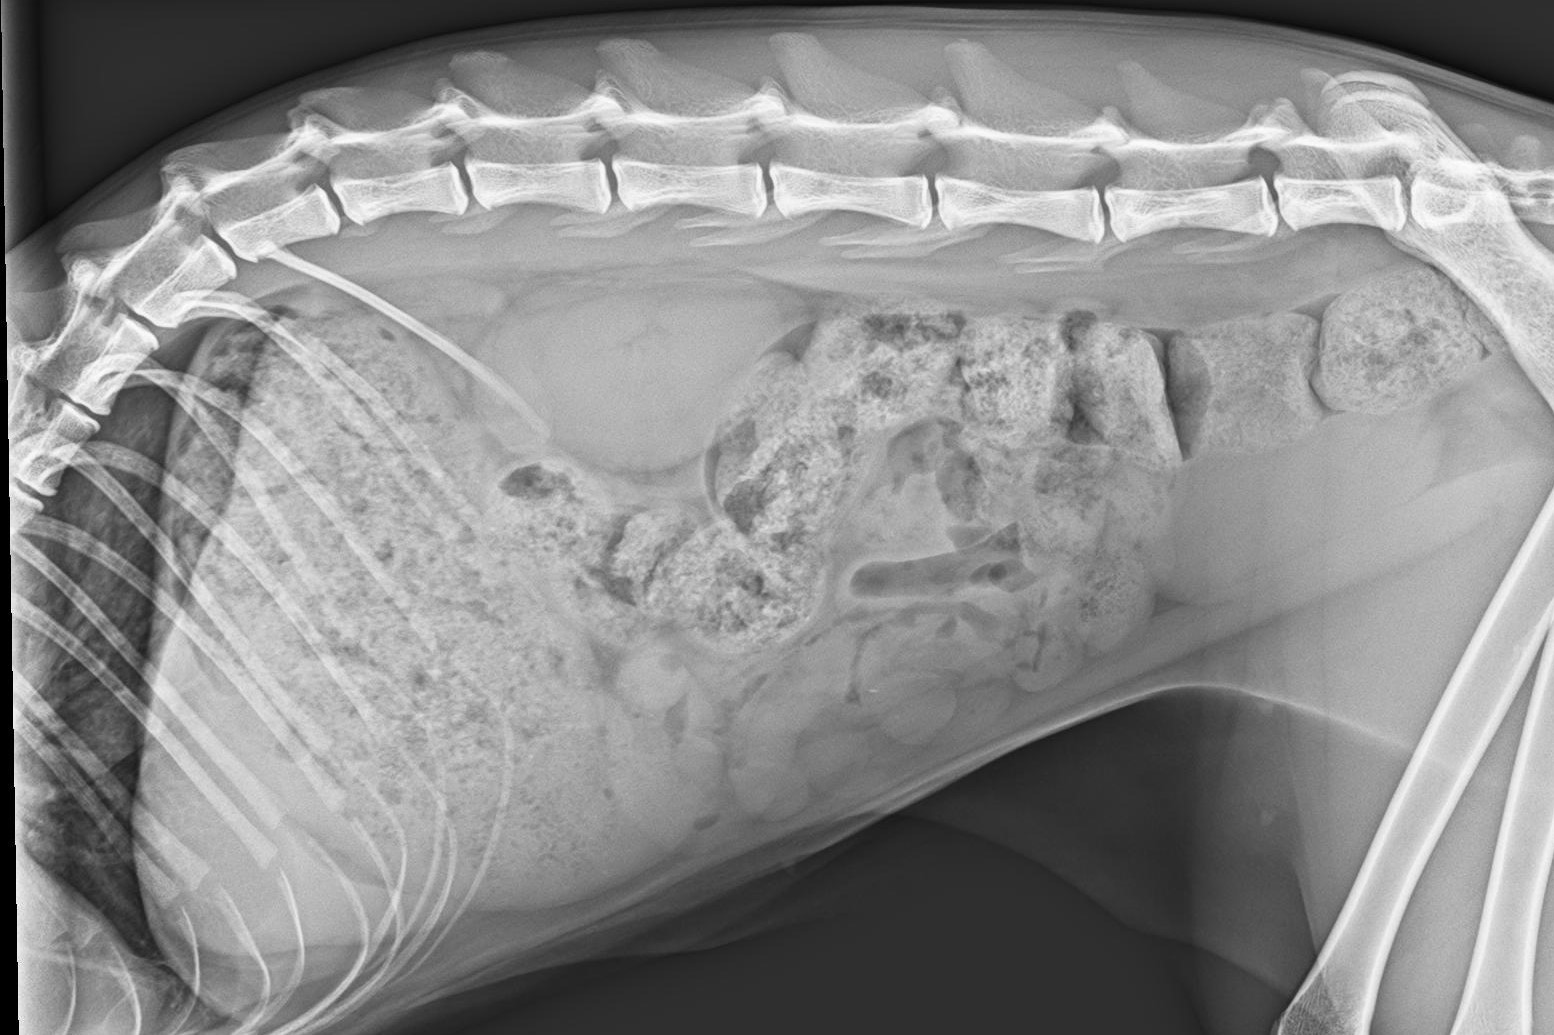

Röntgenaufnahmen des Thorax ergaben keinen abnormen Befund. Die Aufnahmen des Abdomen zeigten einen sehr stark gefüllten Gastrointestinaltrakt und eine relativ kleine Leber (Abb. 1).